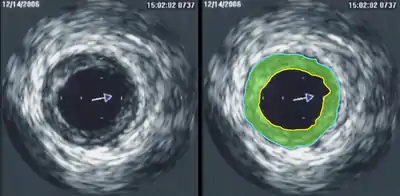

Внутрішньосудинне ультразвукове дослідження (ВСУЗД, англ. IVUS) — метод медичної візуалізації за допомогою спеціального внутрішньосудинного катетера з мініатюрним ультразвуковим датчиком на дистальному кінці. Метод дозволяє за допомогою ультразвукових технологій візуалізувати кровоносні судини зсередини.

Робоча частота дослідження зазвичай становить 20-40 МГц. У наконечнику катетера знаходиться блок трансдюсера, що випромінює та сприймає відбиті ультразвукові хвилі. Через кабель передачі даних ця інформація надходить до системного блоку УЗ-апарату. Він створює зображення поперечного перерізу судини навколо катетеру у режимі реального часу (зазвичай з частотою 30 кадрів/сек). Протягом всього дослідження відбувається запис даних. Проводиться одночасний моніторинг ЕКГ.

Внутрішня стінка кровоносних судин, склеротична бляшка на стінці і сполучна тканина, що покриває зовнішню поверхню кровоносних судин є ехогенними, тобто видимими для ультразвуку. Кров і здорова м'язова тканина (частина стінки кровоносних судин) значною мірою поглинають ультразвук і при візуалізації дають просто чорні кола.

Важкі відкладення кальцію в стінках кровоносних судин сильно відбивають звук, тобто дуже ехогенності, і при УЗД виглядають як дуже яскраві ділянки з тінню позаду (відповідно до положення катетера, що випромінює ультразвукові хвилі).